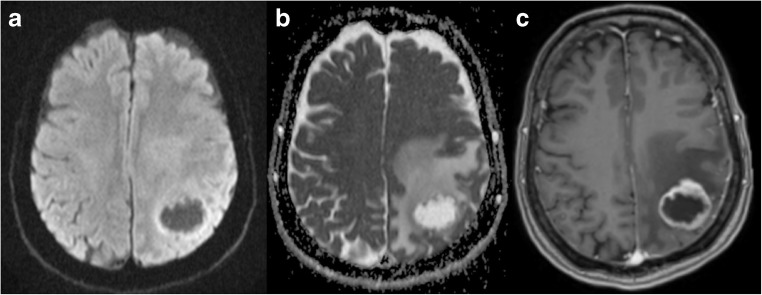

Fig. 8.

GBM. Left parieto-occipital lesion with peripheral vasogenic oedema. DWI and ADC (a and b, respectively) show a clear area of increased diffusion within the core, corresponding to a necrotic centre. On T1 3D post gadolinium the mass shows ring enhancement

Fig. 9.

Subacute haematoma. Right parietal mass (arrowhead) showing diffusion restriction within the core on DWI and ADC maps (a and b, respectively) and a ring-enhancing pattern on T1 post gadolinium (c). This was a subacute haematoma. Clinical context is important to differentiate haemorrhage from abscess. There is also a subacute ischaemic lesion in the inferior right frontal lobe (arrows) that shows early pseudonormalisation of the ADC and gyriform enhancement post gadolinium